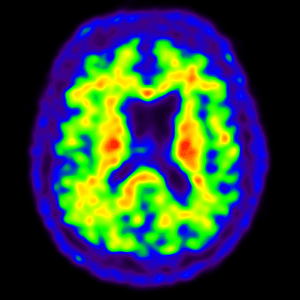

PET mozgu na dôkaz prítomnosti beta-amyloidu

Diferenciálna diagnostika Alzheimerovej demencie